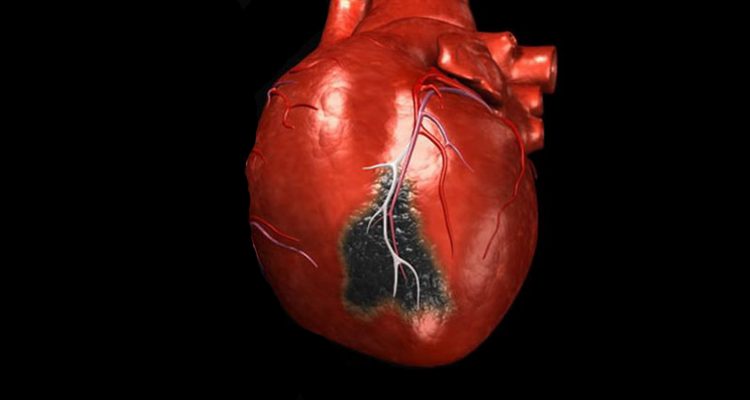

В ході дослідження вчені спостерігали поведінку 2300 добровольців, які перенесли серцевий напад. Пацієнти, які демонстрували такі негативні якості, як ворожість до оточували, цинізм, сарказм і нетерпіння, ризикують отримати повторний серцевий напад в найближчі два роки. Це відбувається, тому що негативні емоції «тиснуть» на серце.

Команда з Університету Теннесі (США) відстежувала поведінку пацієнтів протягом двох років. У вороже налаштованих добровольців відзначалося підвищення рівня холестерину, адреналіну і підвищена серцева реактивність. Ворожість, за словами дослідників, є саме рисою характеру, і тягне за собою образливість і дратівливість.